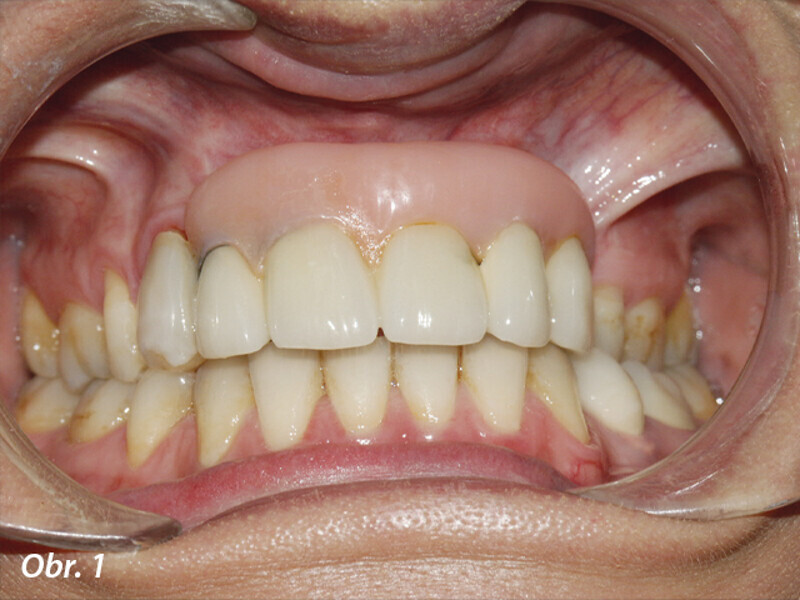

Opětovné implantologické ošetření